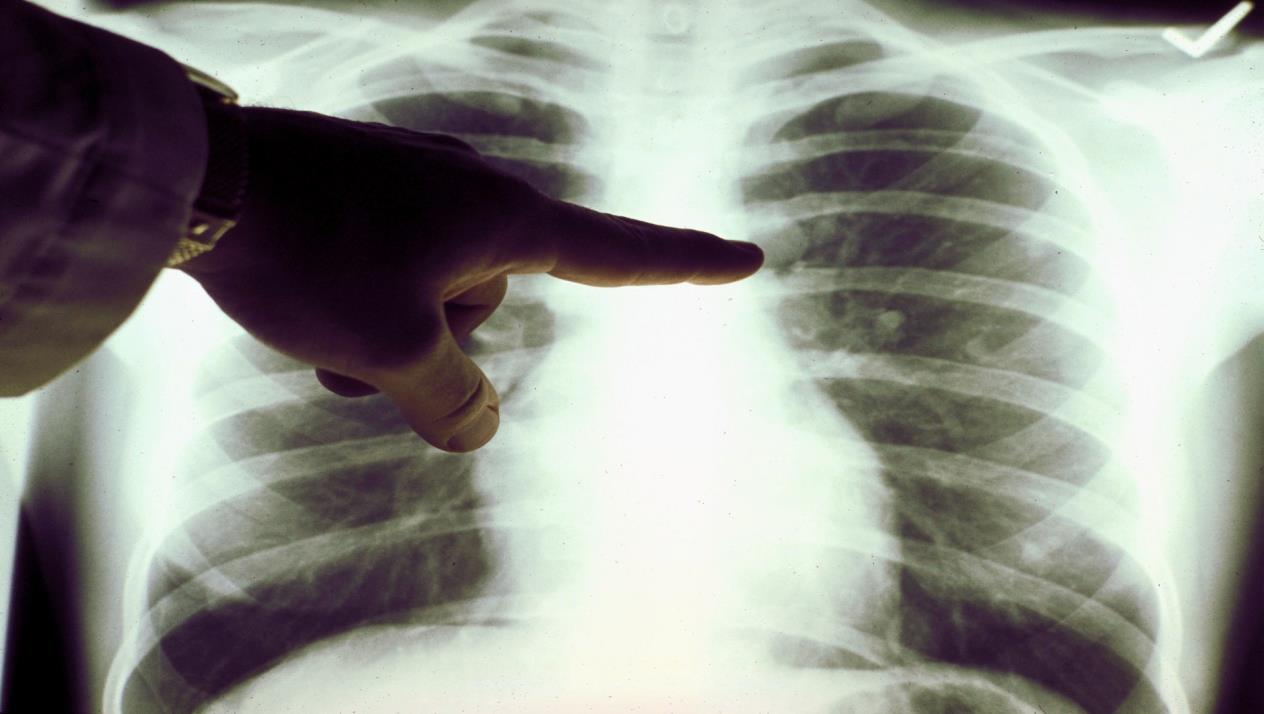

وذكرت صحيفة "ديلي ميل" البريطانية أن باحثي جامعة أوكسفورد خلصوا إلى أن 60% من المتعافين، الذي تم نقلهم إلى المستشفى لإصابتهم بفيروس كورونا، ما زالوا يعانون التهاباً في الرئة بعد مرور ثلاثة أشهر على شفائهم.

وقال الباحثون إن أشعة التصوير بالرنين المغناطيسي أظهرت أن 30% من المتعافين يعانون ضرراً دائماً في الكلى، و26% يعانون ضرراً في القلب، و10% في الكبد.